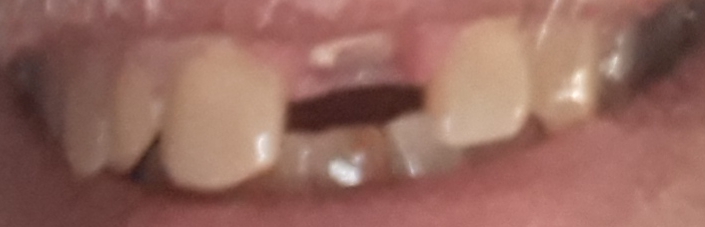

Dente anterior

ImgDenteAtual.jpg